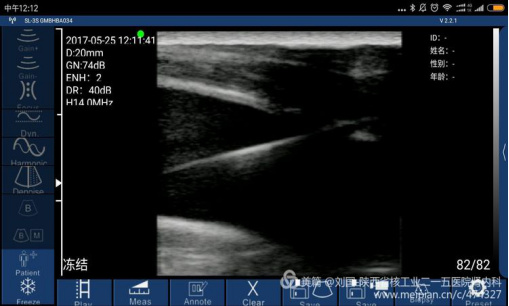

Case 3: Sonostar’s Wireless Ultrasound connected with Mi max by WIFI, synchronously guiding to implant a jugular vein intravenous indwelling catheter with Cuff

Several experiences about using mini wireless ultrasound(Sonostar):

1. It’s better to close the running APP software on mobile phone to confirm the ultrasound software running;

2.For it is connected with the mobile phone as a display by WIFI, image transmission lags. When the display is bad, the operator should slowly move the ultrasound probe, and do not rush, otherwise, a approving image cannot be received.

3.Stumble into the result difference between using iodophor and saline water as coupling agent! Please use saline water!

4.Because there is no color frequency spectrum, the operator cannot judge artery or vein; but the operator cannot judge whether it is artery or vein based on it is compressed or not. The operator should combine physical examination, especial for the peaked patient. I have lessons drawn from my mistakes.